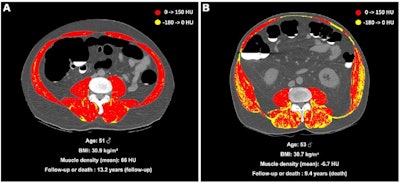

(A) Unenhanced axial abdominal CT image with a Hounsfield unit-based color scale of skeletal muscles in a 51-year-old man with obesity, smoking history, no type 2 diabetes, and no history of cardiovascular events at inclusion shows mild fatty infiltration in the muscles (myosteatosis, yellow), with most voxels in the positive range of Hounsfield units (red). The patient was lost to follow-up after 13.2 years. (B) Unenhanced axial abdominal CT image with a Hounsfield unit–based color scale of skeletal muscles in a 53-year-old man with obesity, smoking history, no type 2 diabetes, and no history of cardiovascular events at inclusion shows severe fatty infiltration in the muscles (myosteatosis, yellow), mostly distributed in the paravertebral (i.e., erector spinae and multifidus) and oblique muscle groups. The patient died after 9.4 years of follow-up. Image and caption courtesy of the RSNA.

(A) Unenhanced axial abdominal CT image with a Hounsfield unit-based color scale of skeletal muscles in a 51-year-old man with obesity, smoking history, no type 2 diabetes, and no history of cardiovascular events at inclusion shows mild fatty infiltration in the muscles (myosteatosis, yellow), with most voxels in the positive range of Hounsfield units (red). The patient was lost to follow-up after 13.2 years. (B) Unenhanced axial abdominal CT image with a Hounsfield unit–based color scale of skeletal muscles in a 53-year-old man with obesity, smoking history, no type 2 diabetes, and no history of cardiovascular events at inclusion shows severe fatty infiltration in the muscles (myosteatosis, yellow), mostly distributed in the paravertebral (i.e., erector spinae and multifidus) and oblique muscle groups. The patient died after 9.4 years of follow-up. Image and caption courtesy of the RSNA.Of the all the study participants, 507 died over the course of three years of follow-up after baseline imaging. The group found myosteatosis in 55% of study participants who died; absolute mortality risk at 10 years in persons with myosteatosis was 15.5% compared to obesity (7.6%), liver steatosis (8.5%), or myopenia (9.7%).